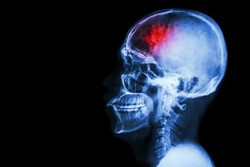

The optimal treatment for regional lymphatic recurrences from head and neck cancer has not been fully established. In this article, Nayel Khan et al. reviewed their experience utilizing interstitial brachytherapy (IBT) at the M. D. Anderson Cancer Center in order to explore the therapeutic benefit of surgical resection and adjuvant brachytherapy.